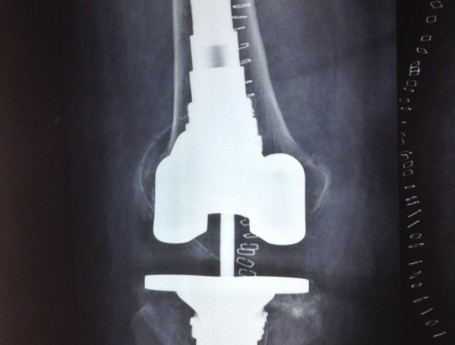

Revision Total Knee Replacement After a fructure

• Revision Total Knee Replacement After a fructure